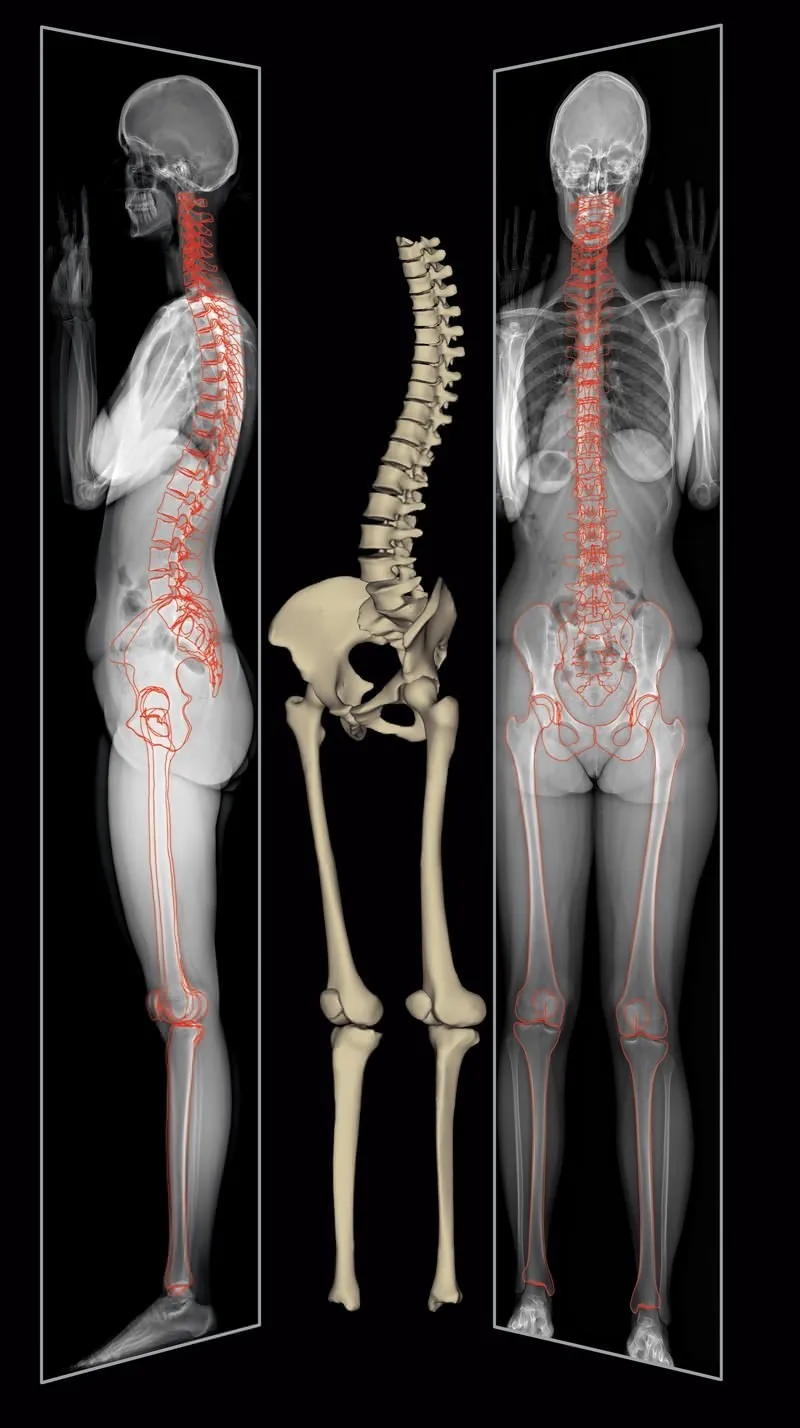

Modélisation 3D surfacique semi-automatique

Le logiciel SterEOS permet une reconstruction 3D surfacique semi-automatique à partir des deux clichés face/profil basse dose en charge. Cette reconstruction permet la mesure automatique de plus de 100 paramètres cliniques, sans facteur d’agrandissement et de façon parfaitement reproductible. Elle permet une analyse posturale globale et reproductible.

Contrairement au scanner qui se fait allongé, les modélisations 3D sont obtenues en position verticale, ce qui permet d’avoir un diagnostic amélioré possible uniquement lorsque le patient est en position fonctionnelle debout. La modélisation SterEOS 3D permet l’affichage de la position, de la rotation et de l’orientation des structures osseuses, ainsi que le calcul de plus de 100 paramètres cliniques pertinents pour la planification chirurgicale et le suivi des pathologies.